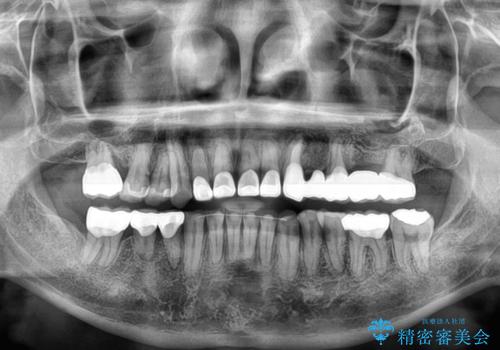

矯正治療は想定通り長期化しましたが、しっかりと奥歯の咬み合わせを向上させて前歯の被蓋を改善させることができました。

目立つ銀歯やすり減った前歯がセラミッククラウンとなり、患者様には大変満足していただけました。